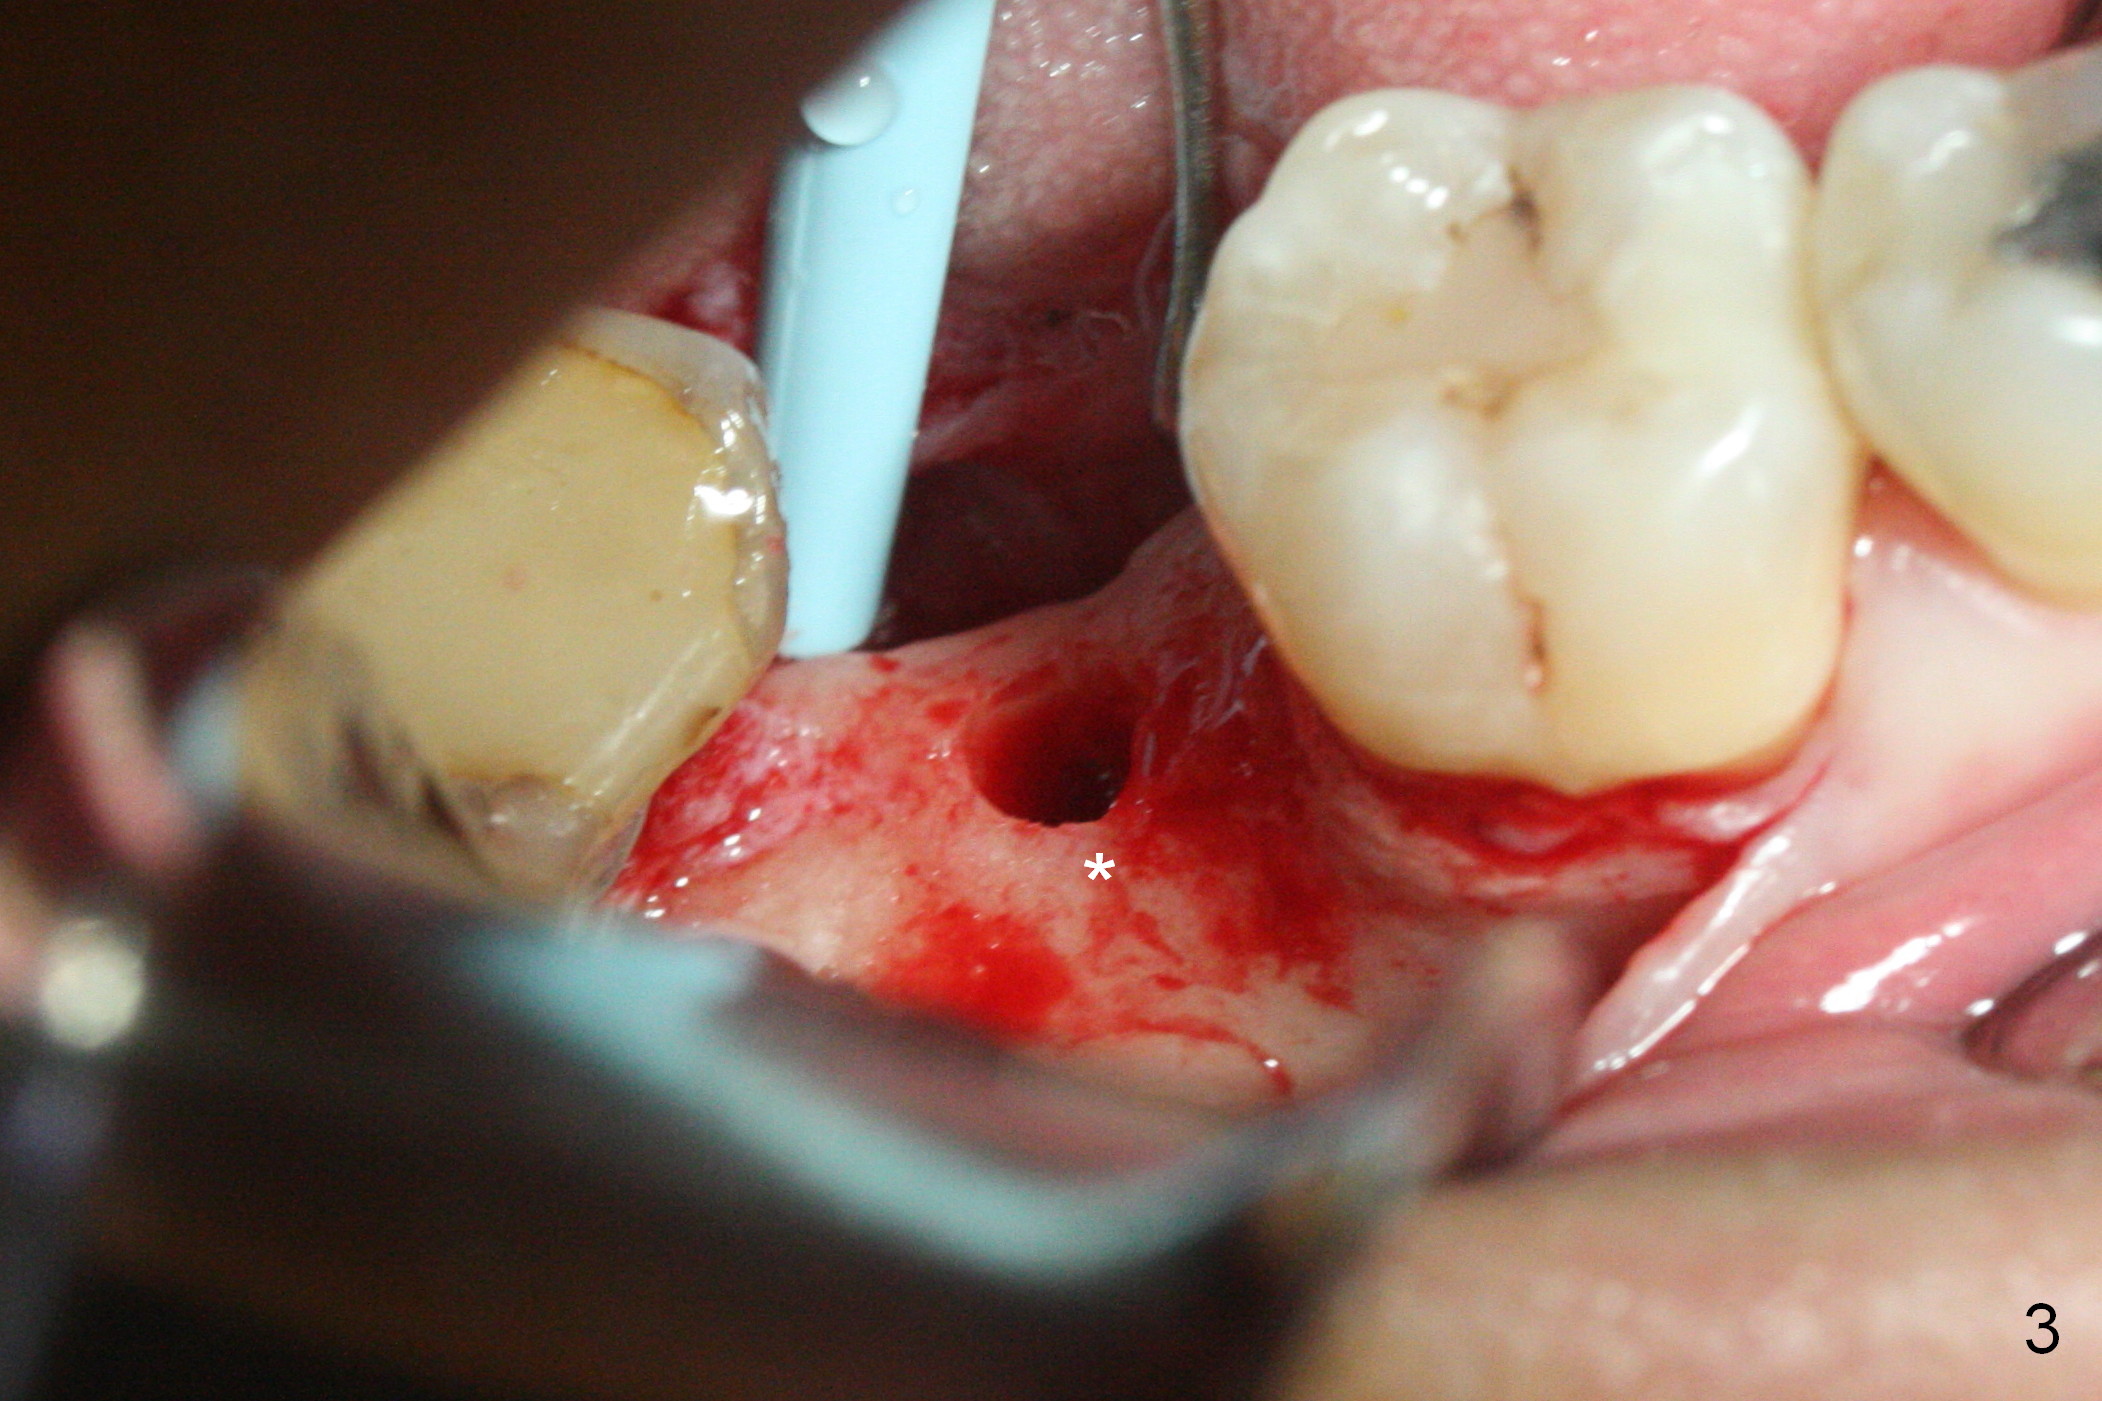

The ridge at #31 is also narrow buccolingually (Fig.1 *).  After incision and 1.6 mm pilot drill, a guide pin with 7 mm length is inserted to confirm trajectory and depth; it appears that 11 mm osteotomy has enough clearance from the superior border of the Inferior Alveolar Canal (IAC, Fig.2 red dashed line).  Following Marking Bur, 3.3 mm Magic Drill and final drill, the buccal plate seems to be thin (Fig.3 *).  When a 4x11 mm IBS implant and 5x4(2) mm pair abutment are placed, the distal thread is exposed (Fig.4 >), the abutment contacts the opposing tooth (data not shown) and there is 2.7 mm clearance from IAC.  After increasing the osteotomy 1-2 mm, the implant is placed deeper; the autogenous bone with Osteogen is placed around the plateau of the implant (Fig.5 >), particularly buccally, followed by collagen membrane.  When sutures are placed around the abutment, the buccal ridge looks bulkier (Fig.6) than preop (Fig.1).  It may remains so long term.  The flap surgery makes it possible for simultaneous GBR and reduction in possibility of peri-implantitis.  Last, periodontal dressing is applied.